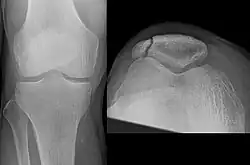

Manchmal macht die röntgenologische Abgrenzung der Patellafraktur von einer Patella partita (lat.: zweigeteilte Kniescheibe), also einer während der Entwicklung ausgebliebenen Verschmelzung der Knochenkerne, diagnostische Schwierigkeiten. Während sich frische Frakturen scharfkantig abbilden, findet man bei der Patella partita abgerundete Kanten, die „Fragmente“ sind nicht miteinander kongruent. Auch fehlt bei der Patella partita in der Regel der typische klinische Befund einer Patellafraktur, es besteht keinerlei Funktionsverlust. Wichtig ist die Unterscheidung für die Indikation zur Operation: Nur die frische Fraktur profitiert von der OP.

Differentialdiagnose Patella bipartita: Im Gegensatz zur Längsfraktur (s. unten) abgerundete Kanten der Fragmente -

Differentialdiagnose Riss der Patellarsehne: Zeichen im Röntgenbild: Hochstand der Patella.